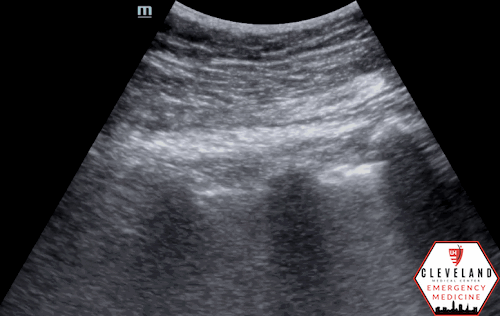

Normal lung sliding (lateral and inferior chest)

Assessment for pneumothorax on lung ultrasound centers on evaluation of pleural motion rather than direct visualization of intrapleural air (7,8). After identifying the pleural line, first assesses for pleural sliding (Figure 2), which reflects normal apposition of the visceral and parietal pleura; its presence effectively rules out pneumothorax at that location (5,7). Because air preferentially accumulates in the least dependent regions of the lung, focusing the initial assessment in these areas provides the highest diagnostic yield.

Figure 2. Normal lung sliding